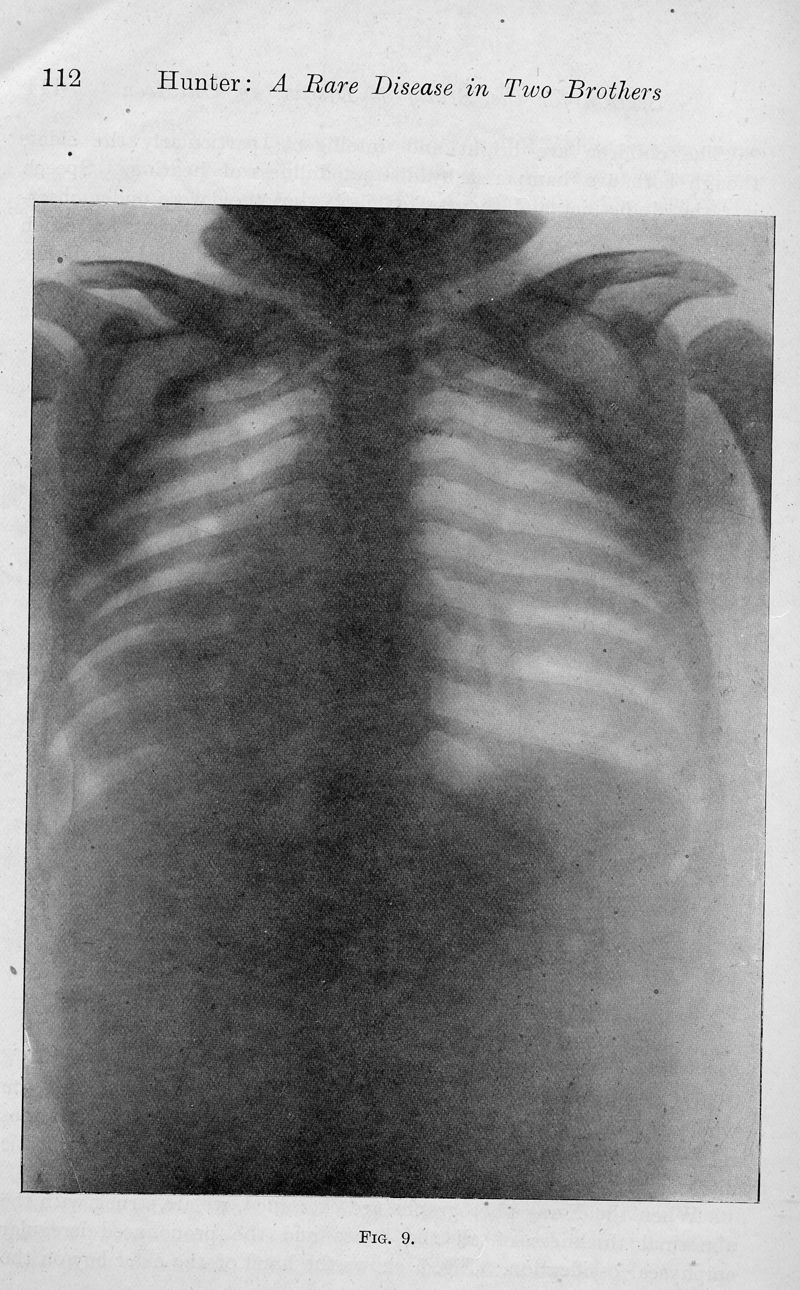

HUNTER, Charles.

In : Proceedings of the Royal Society of Medicine, 1917, Vol. 10, pp. 104-16